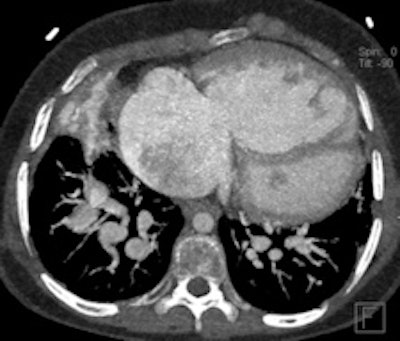

Retrospective ECG-gated study on a 5 year old with severe pulmonary hypertension. The CT images show dilated pulmonary arteries (top left). There is right atrial and ventricular dilatation with hypertrophy and bowing of the interventricular septum into the left ventricle (arrow, top right). There is abnormal arborization and angulation of the peripheral pulmonary arteries (top right, bottom), with multiple peripheral centrilobular nodules with perilesional ground-glass attenuation. Features are in keeping with pulmonary capillary hemangiomatosis.